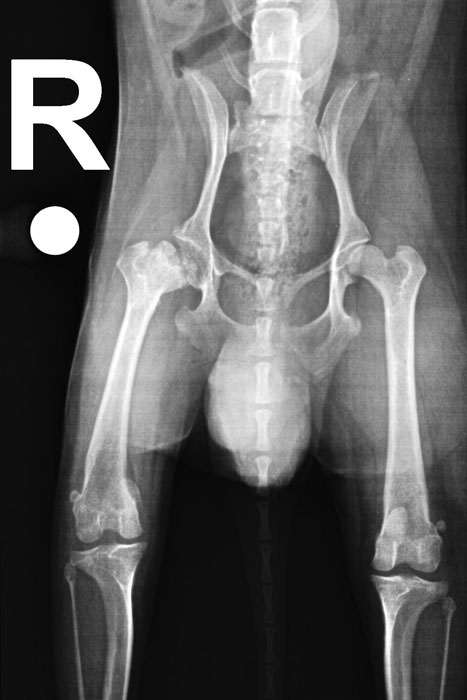

Vor der OP: Oberschenkelkopf löst sich auf.